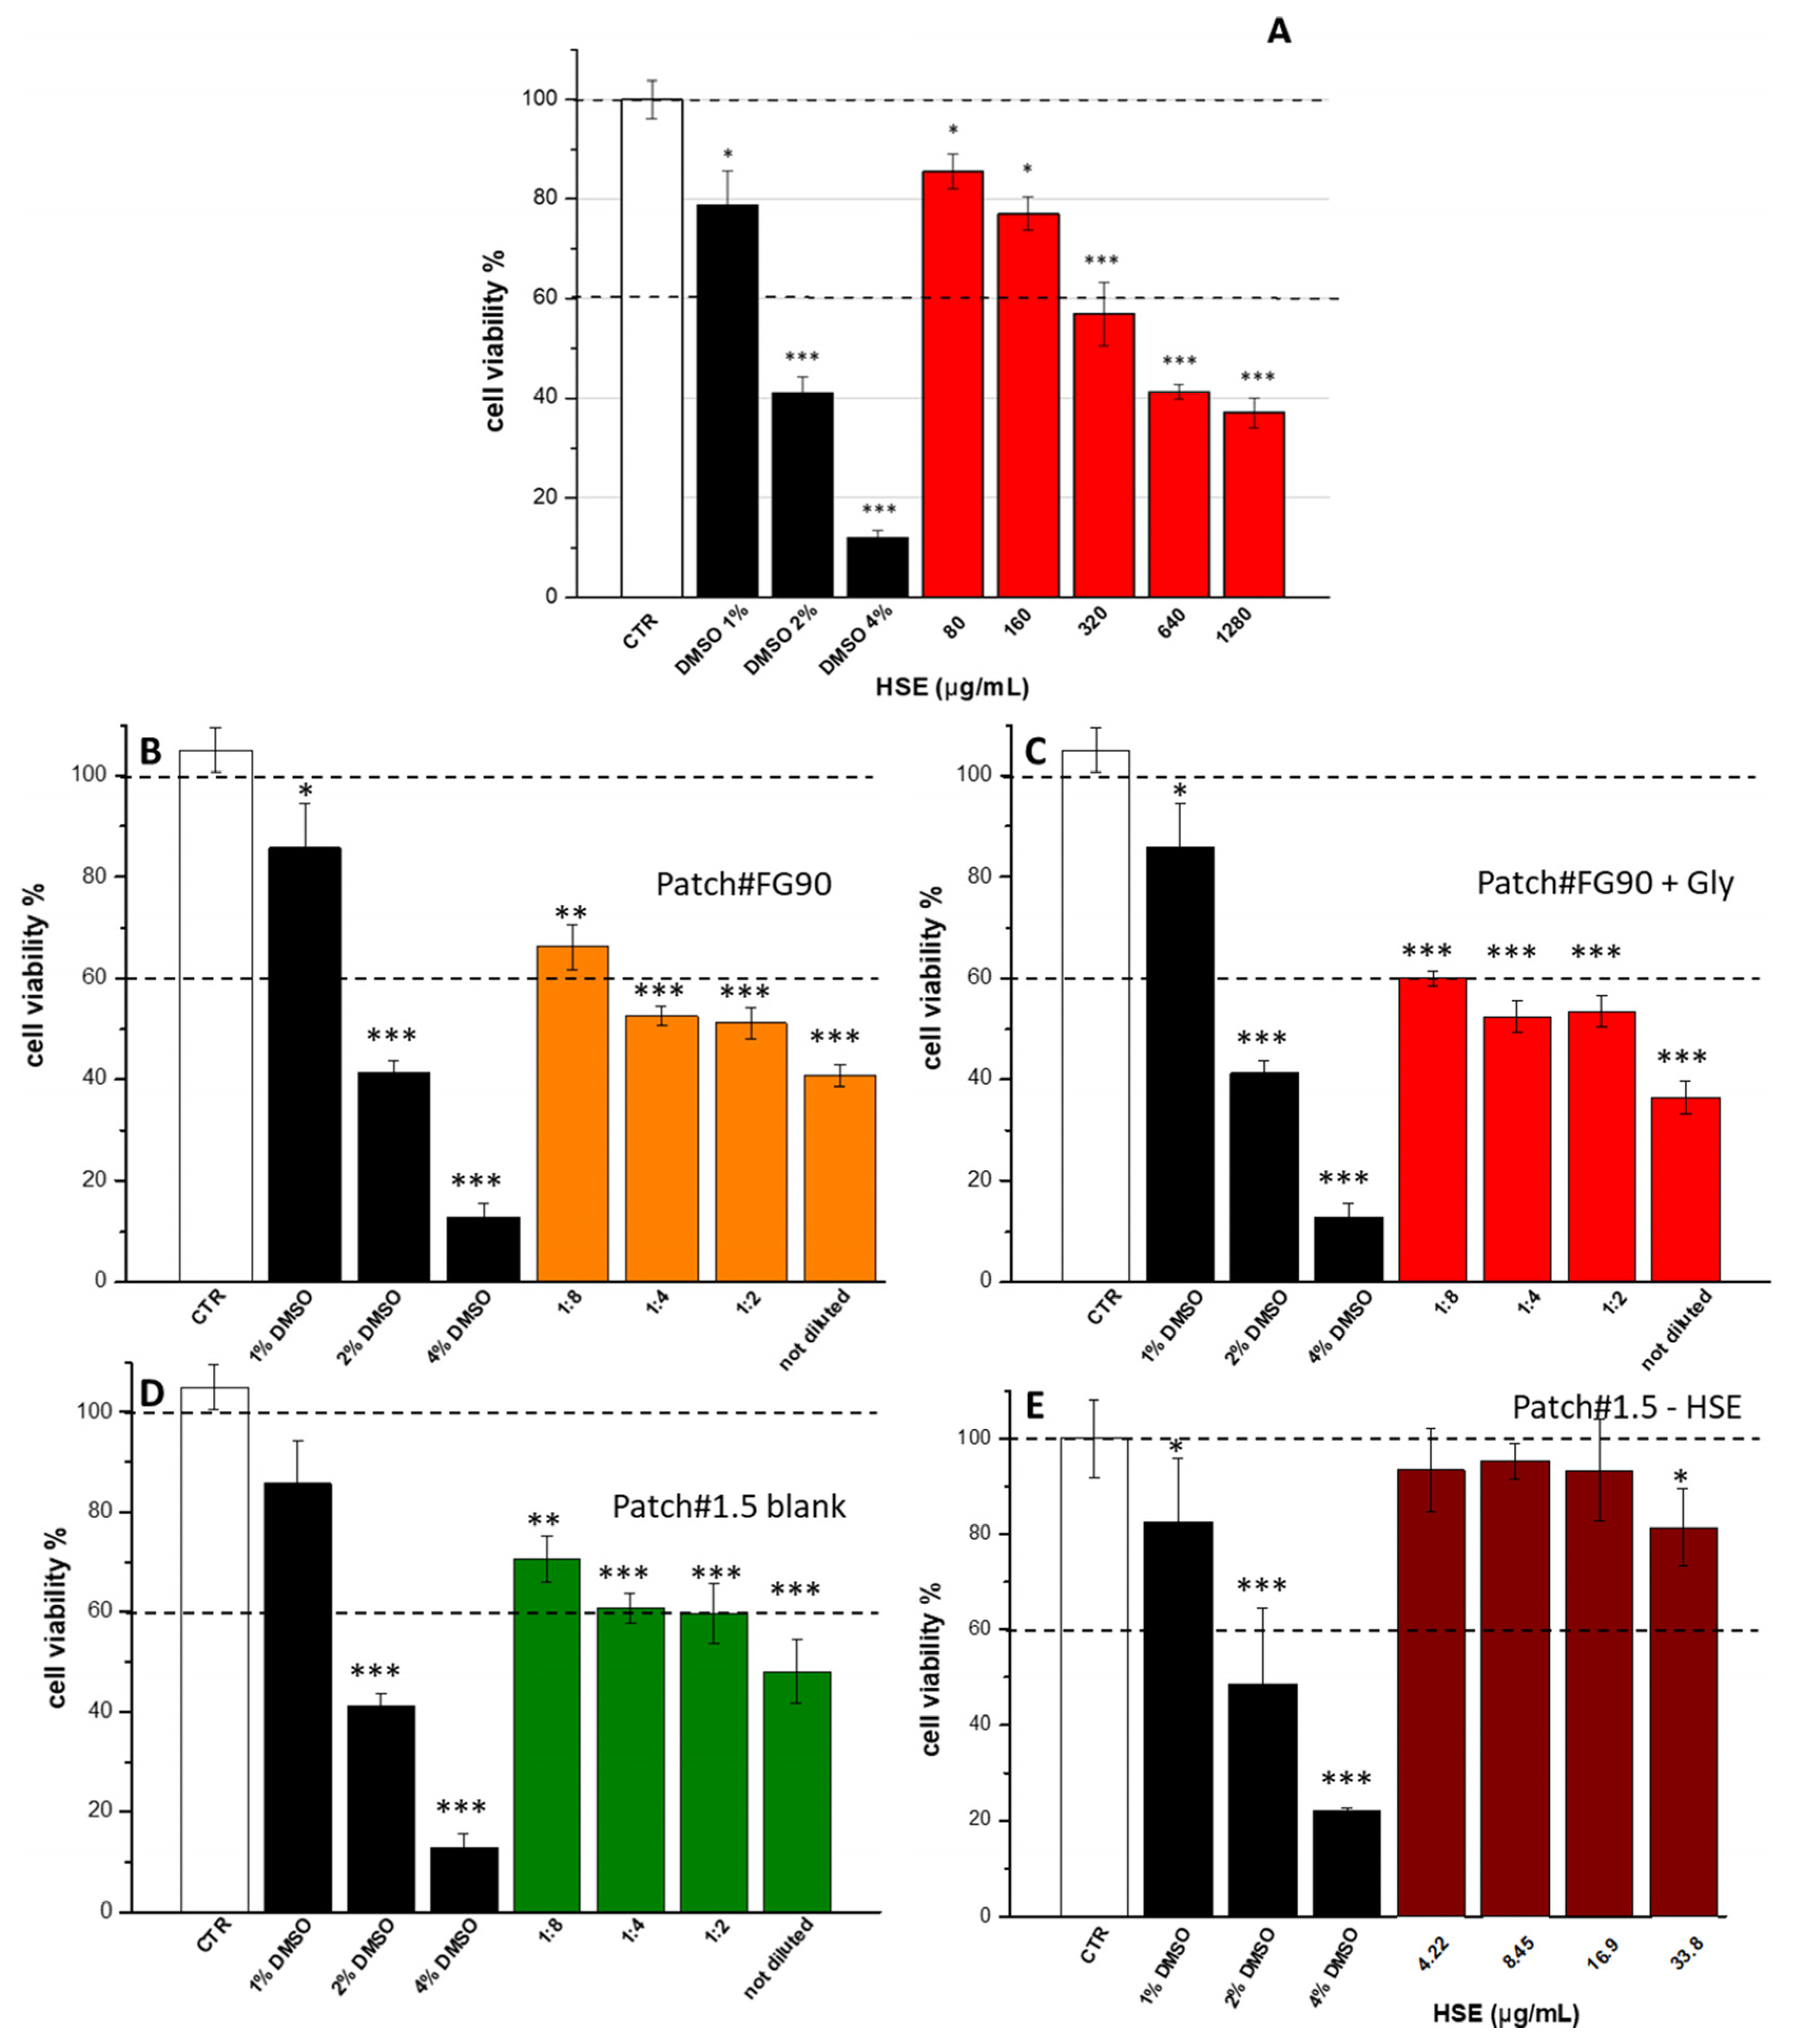

3.5. Cytotoxic Activity

3.6. Loaded Patch Characterization